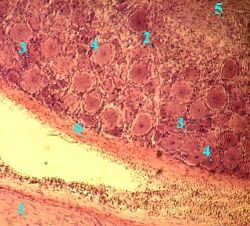

Препарат 8.

Спинномозговой узел. Окраска гематоксилин-эозином.

А. Топография снимка

Прежде чем обсуждать строение узла, полезно разобраться во взаиморасположении   соответствующих структур:

а) слева от снимка должен находиться

спинной мозг (не попавший в препарат);

б) внизу снимка -

передний корешок (1) спинного мозга (по которому из мозга выходят

а) Малое увеличение

аксоны мотонейронов и

преганглионарные волокна вегетативной нервной системы);

в) вверху -

задний корешок (2) спинного мозга и в нём -

спинномозговой узел (3), образующий в этом корешке утолщение;

г) справа - т.н. бифуркация, где передний и задний корешки объединяются в

спинномозговой нерв (который далее распадается на несколько смешанных нервов).

Б. Топография узла

а) Снаружи спинномозговой узел покрыт

соединительнотканной капсулой (6),

в которой находятся кровеносные сосуды.

Прослойки соединительной ткани (вместе с сосудами) проникают и внутрь узла.

б) В спинномозговом узле находятся

тела чувствительных нейронов (4).

При этом они располагаются группами на периферии узла.

в) В центре узла (между группами нейронов) проходят

нервные волокна (5), содержащие

отростки чувствительных нейронов.